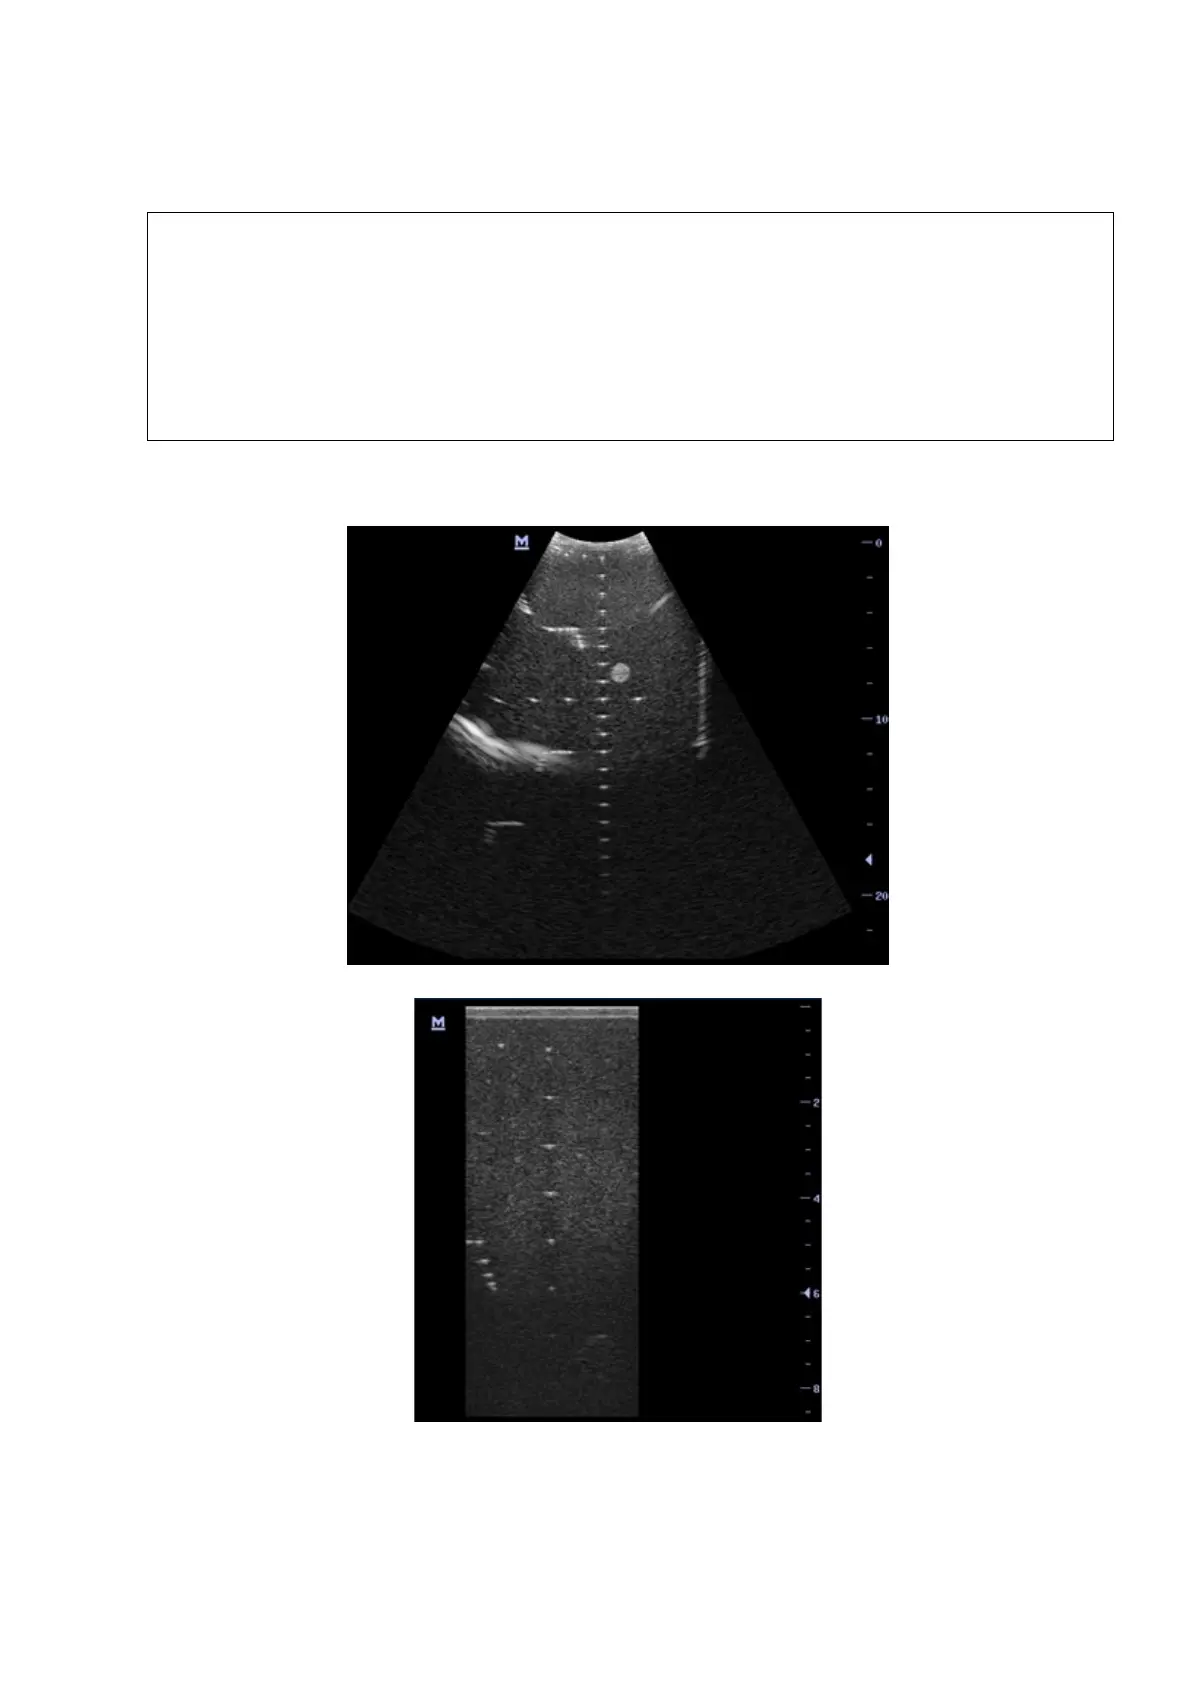

5-14 Function and Performance Checking Method

5. Record the depth of the furthest target (the target can be seen clearly).

As shown in figure below.